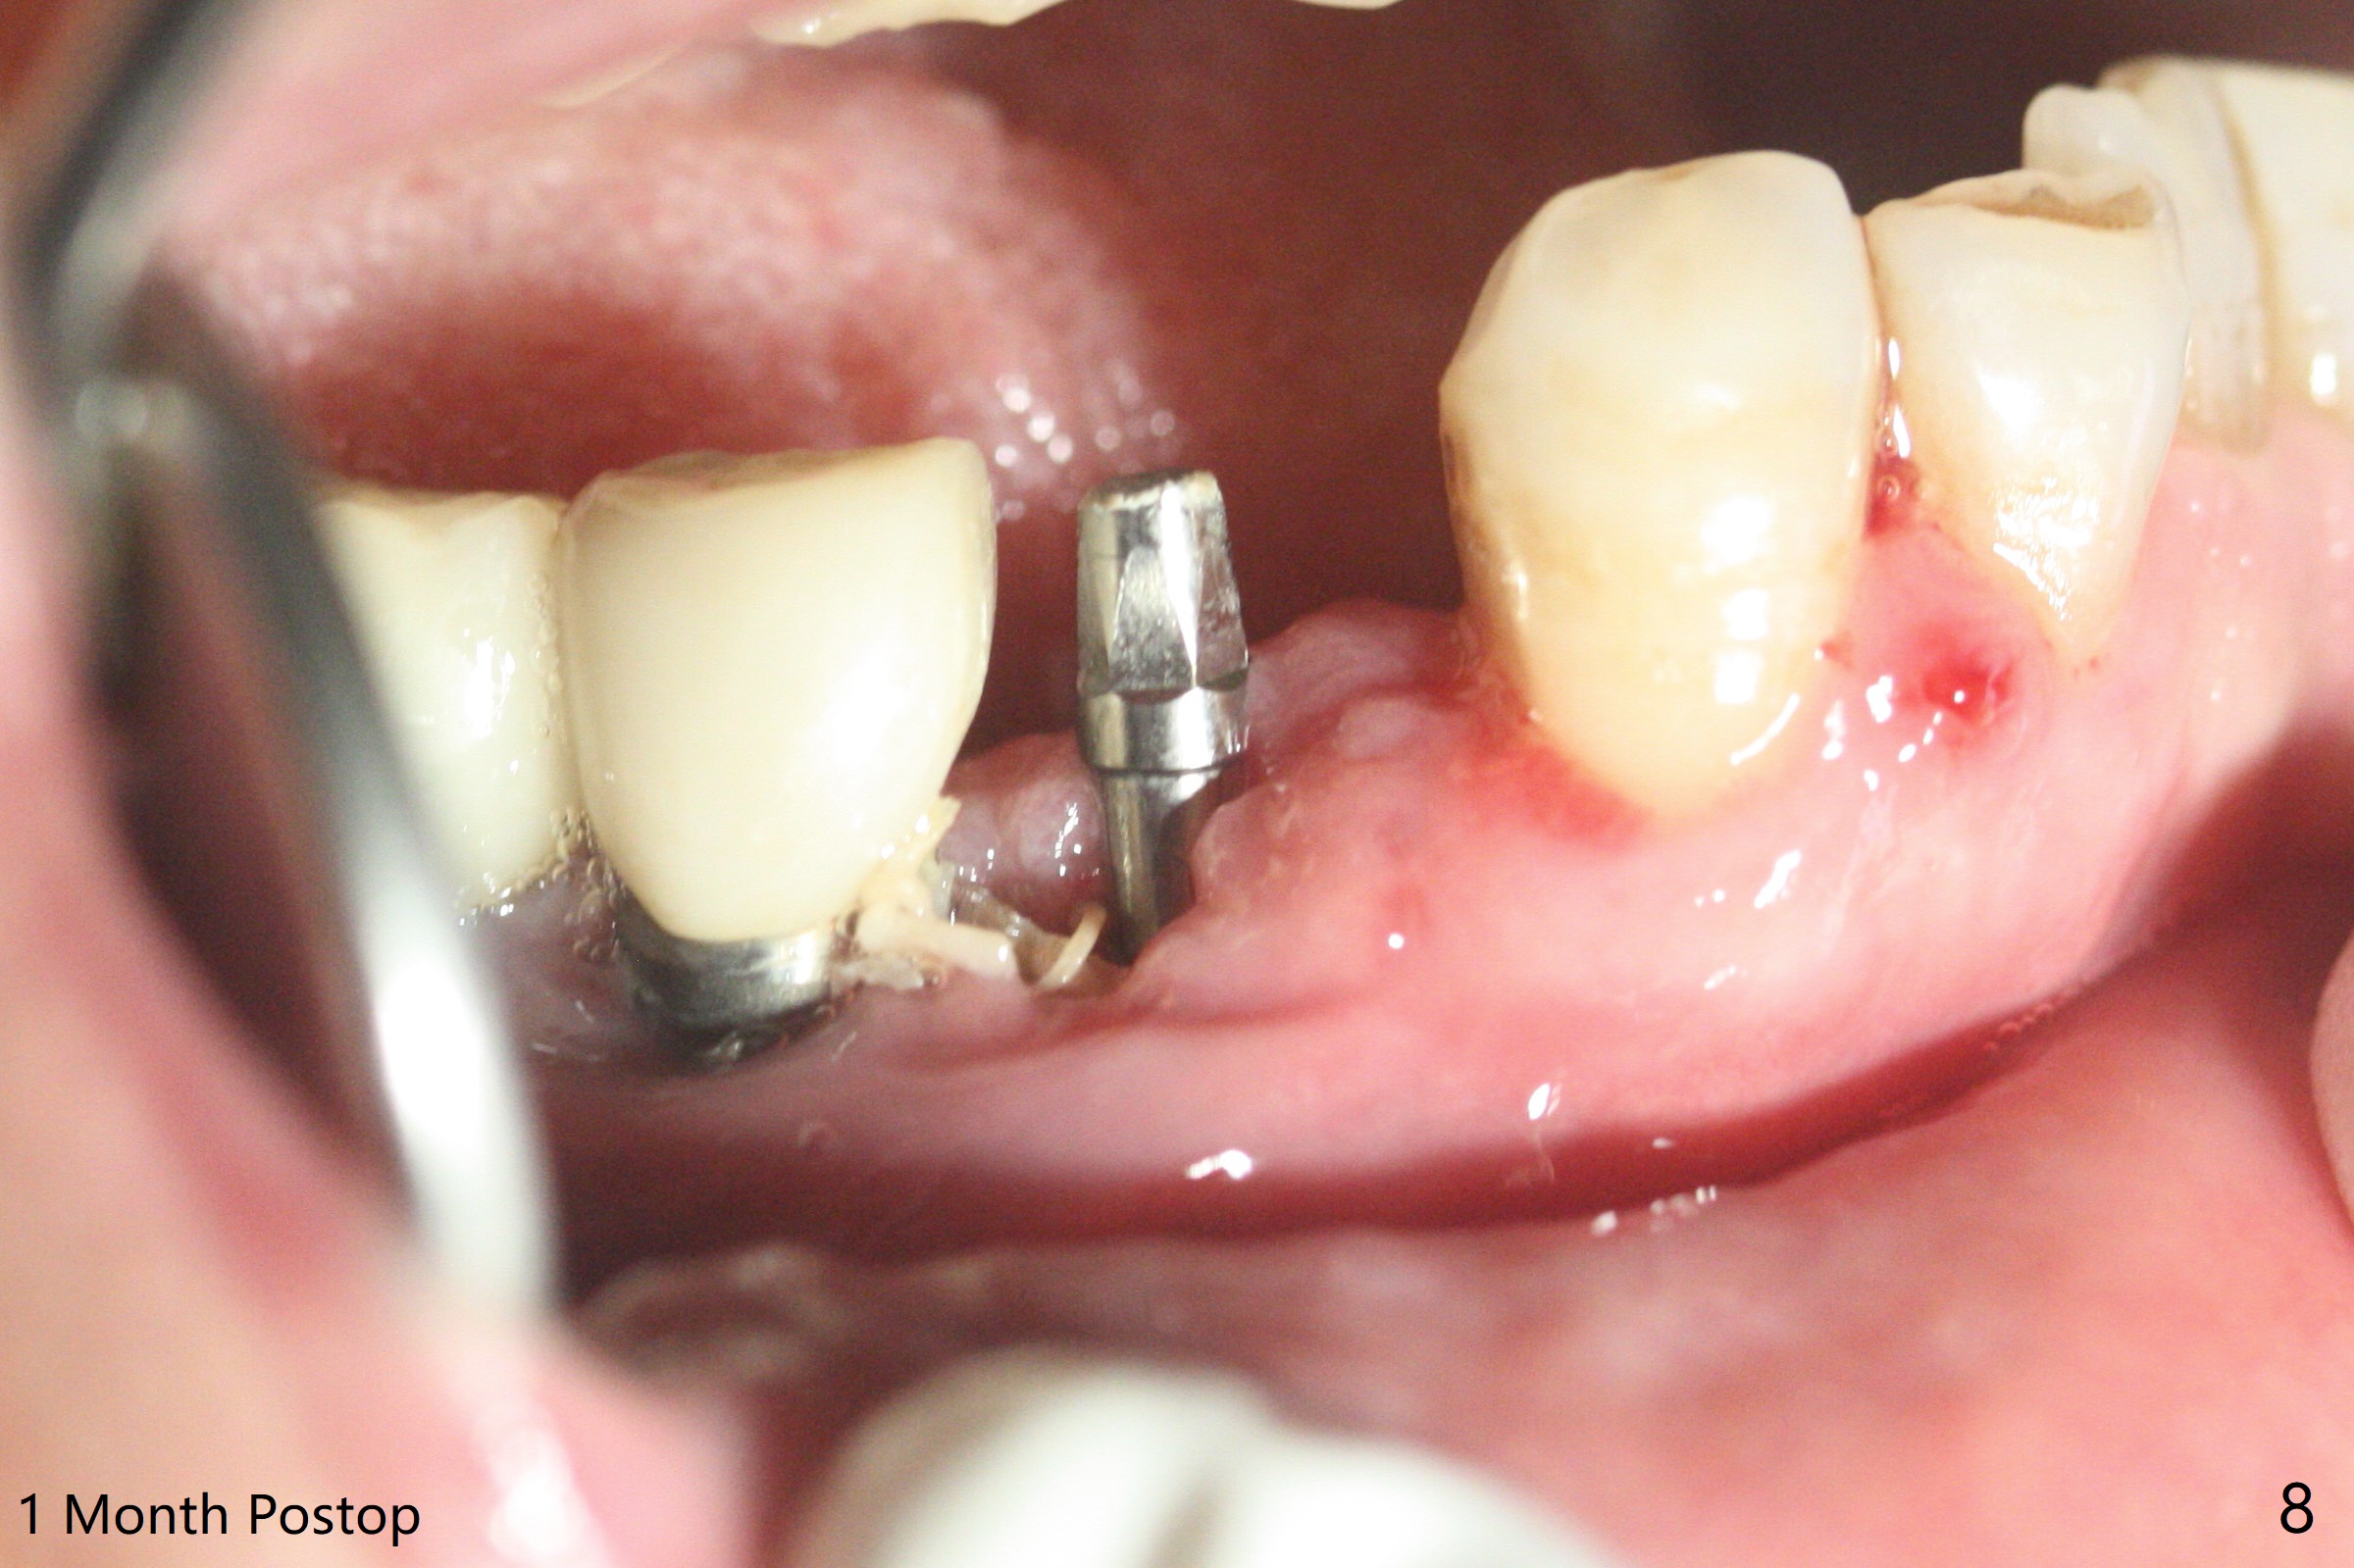

61岁女右下4(粘固后5.5年)植体周围炎(颊侧牙龈没有角化龈(图一:*)),因为颊侧种植(图二),翻瓣证实(图三),取出4.5毫米两段式植体,在舌侧骨质(图四:L)即刻植入2.5毫米一段式植体(图五),颊侧缺损植入大量粘性骨粉(图六:*),覆盖PRF膜后,缝合(图七),与图二对比,窄植体明显舌侧移位。术后一个月撤除牙周敷料(图八),并没有马上制作临时牙冠,让病人容易搞好局部卫生,促进伤口愈合(图九),术后三个月塞入龈线(图十:^),制备基台,植体在牙槽嵴中性位置(颊舌侧),但愿颊侧有足够再生骨质,覆盖植体螺纹。